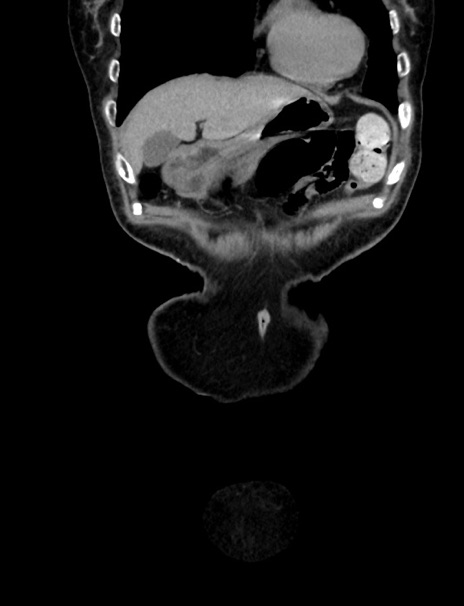

症例33(冠状断像)

【症例】70歳代 女性

【主訴】心窩部痛

【現病歴】延髄病変の精査・加療にて神経内科入院中。本日より心窩部痛あり。

【身体所見】右下腹部を中心に圧痛と反跳痛あり。

【データ】WBC 10900、CRP 0.02